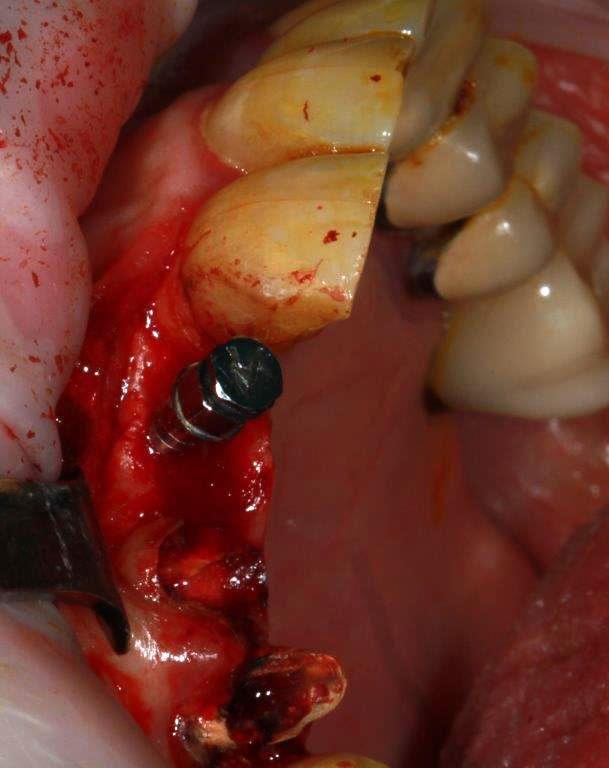

15/01/2019 à 19h14

zone prête pour l’implant